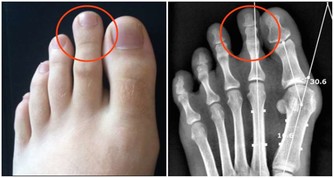

① 正面(男士姿勢)

1.飯後,找一堵牆,最好有一個舒適的靠墊(不可太軟)。站在牆前,屈膝下蹲,背須要直,貼靠牆壁或靠在軟墊上。

2.注意男女姿勢的差別:

女士姿勢:兩腳併攏,屈膝下蹲。

男士姿勢:兩腳微微分開(兩腳不可完全併攏),屈膝下蹲,這樣可以放鬆襠部,不會使襠部過緊。

3.雙手結孔子手印,自然放在膝蓋上,放鬆身心。

4.頭要中正,頭頂百會與會陰穴成一條直線,臀部離地,緊壓小腿肚上。